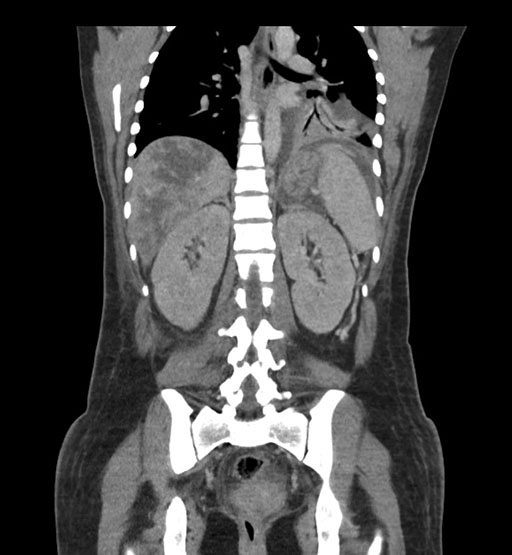

Coronal Venous